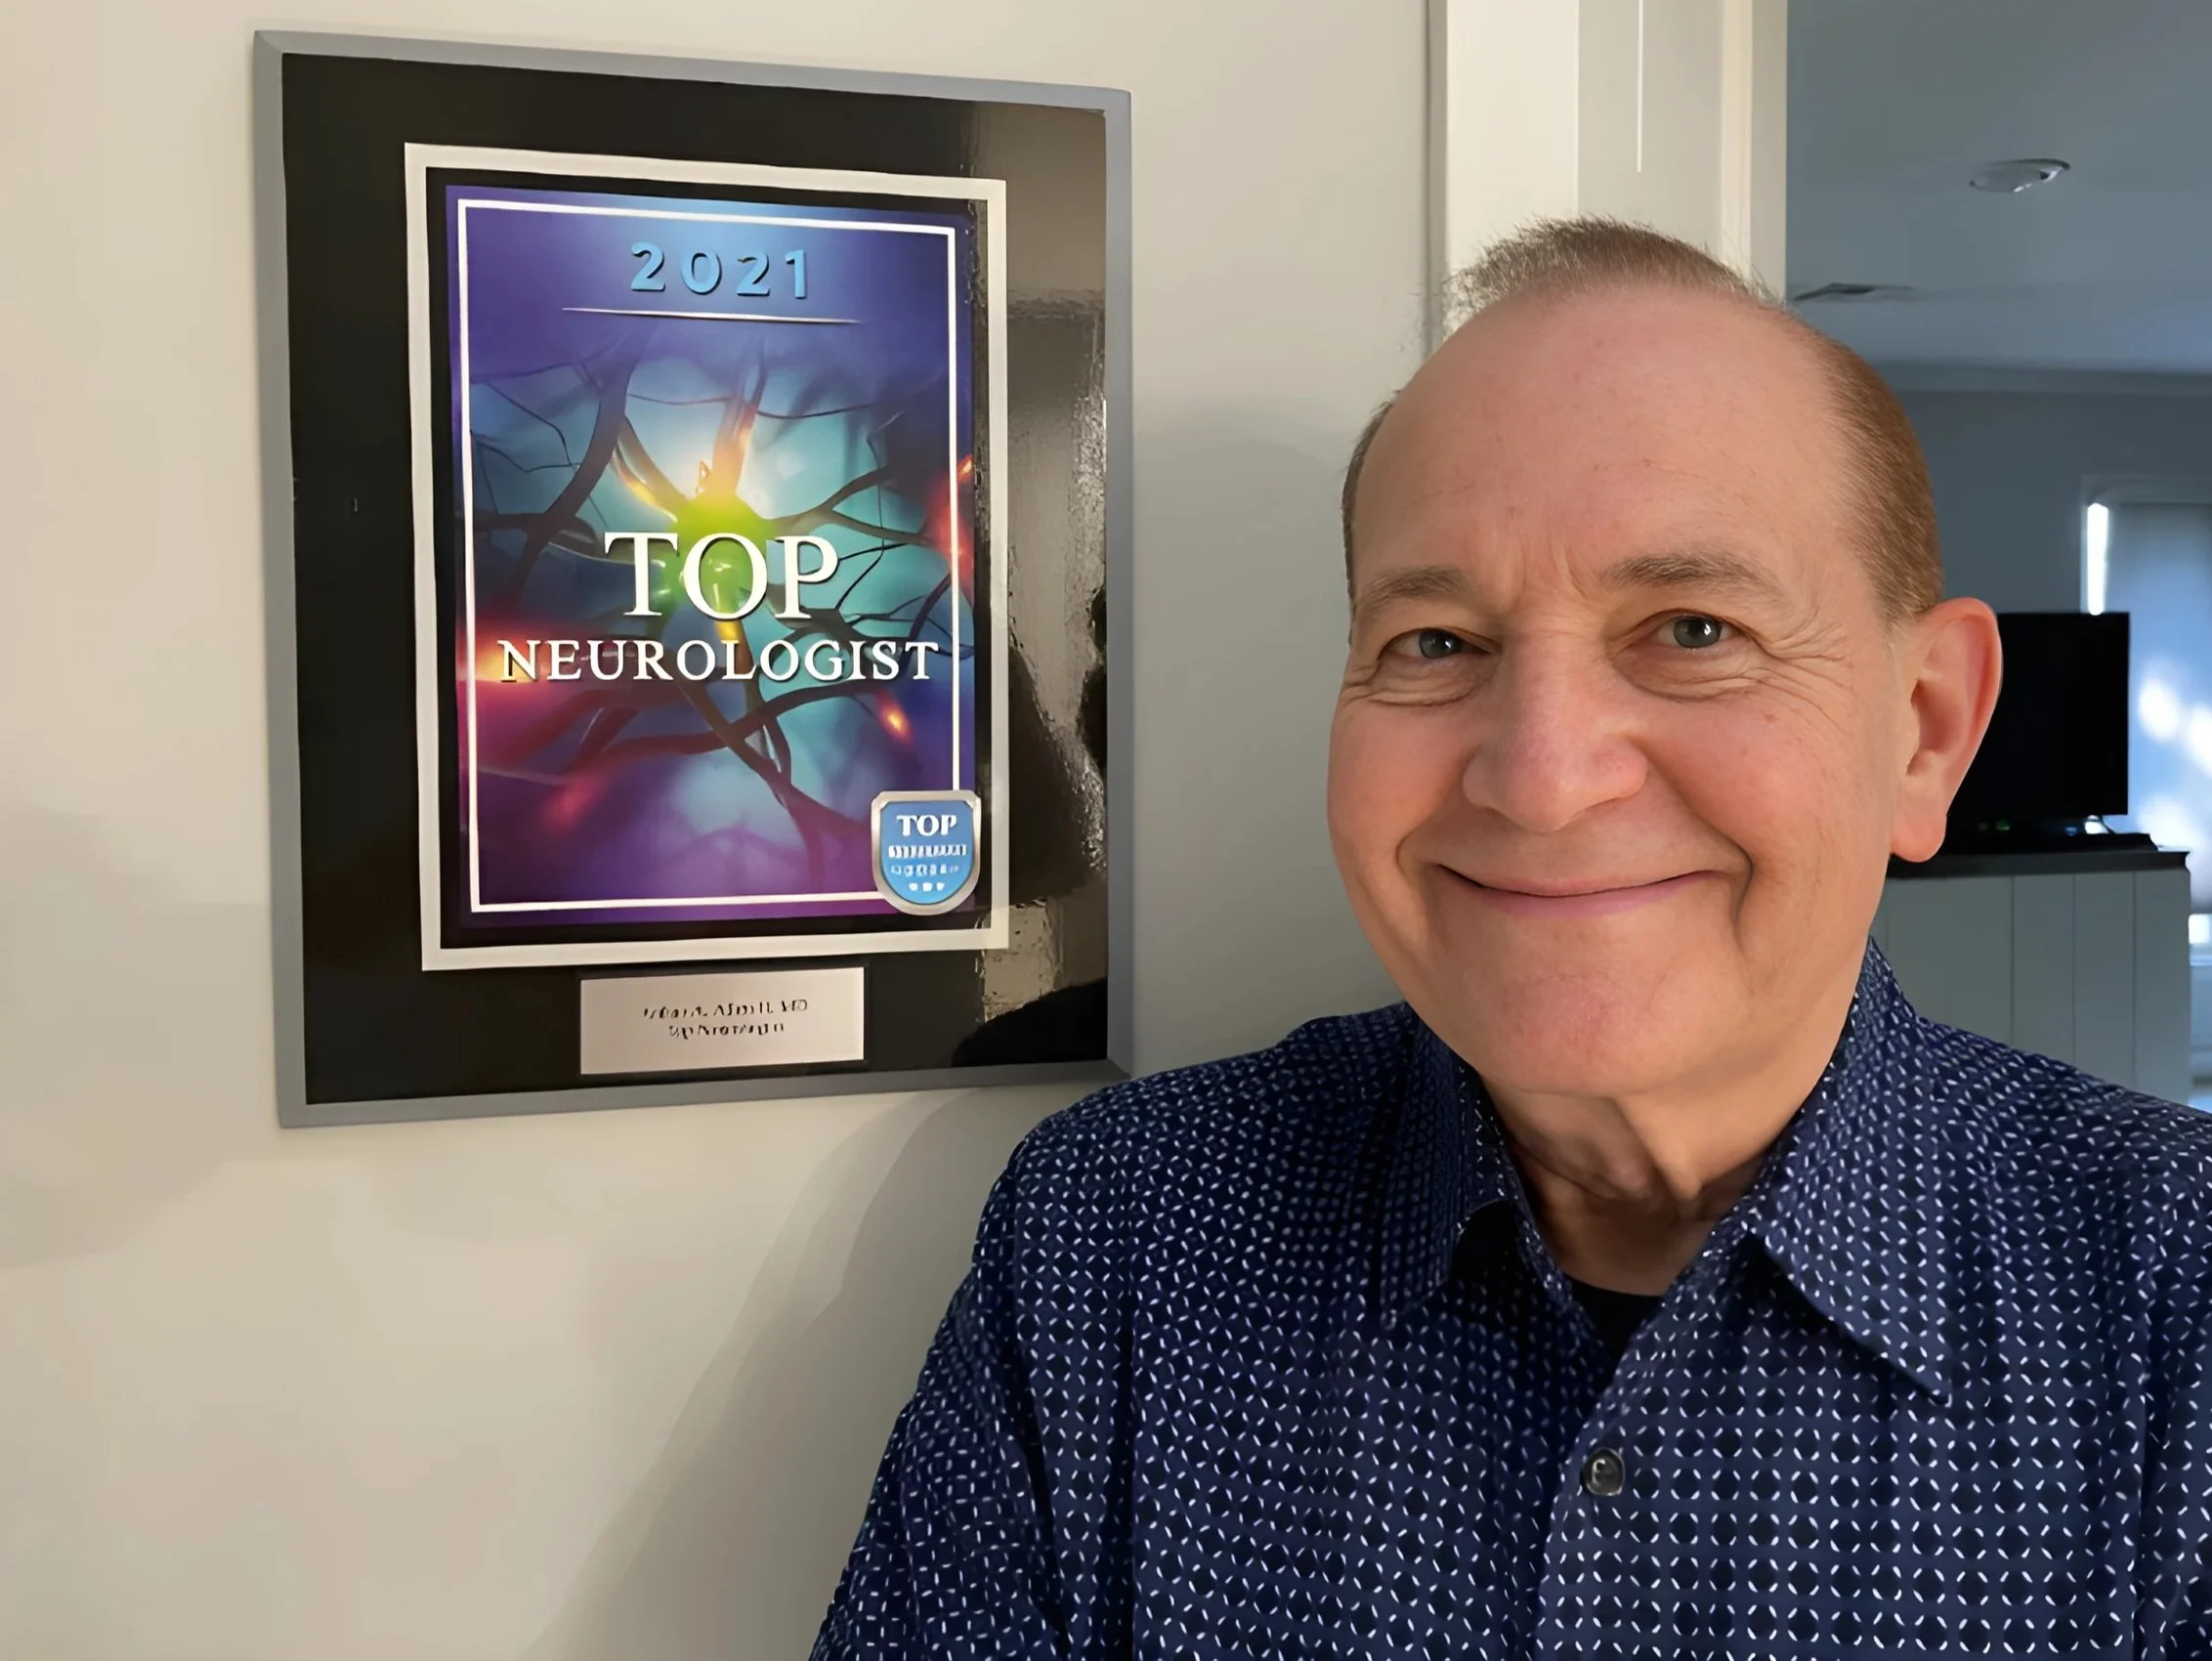

Arthur A. Allen II, M.D.

Dr. Allen is a board certified Neurologist with over four decades of practice diagnosing and treating neurological disorders.

Dr. Arthur A. Allen II, M.D.